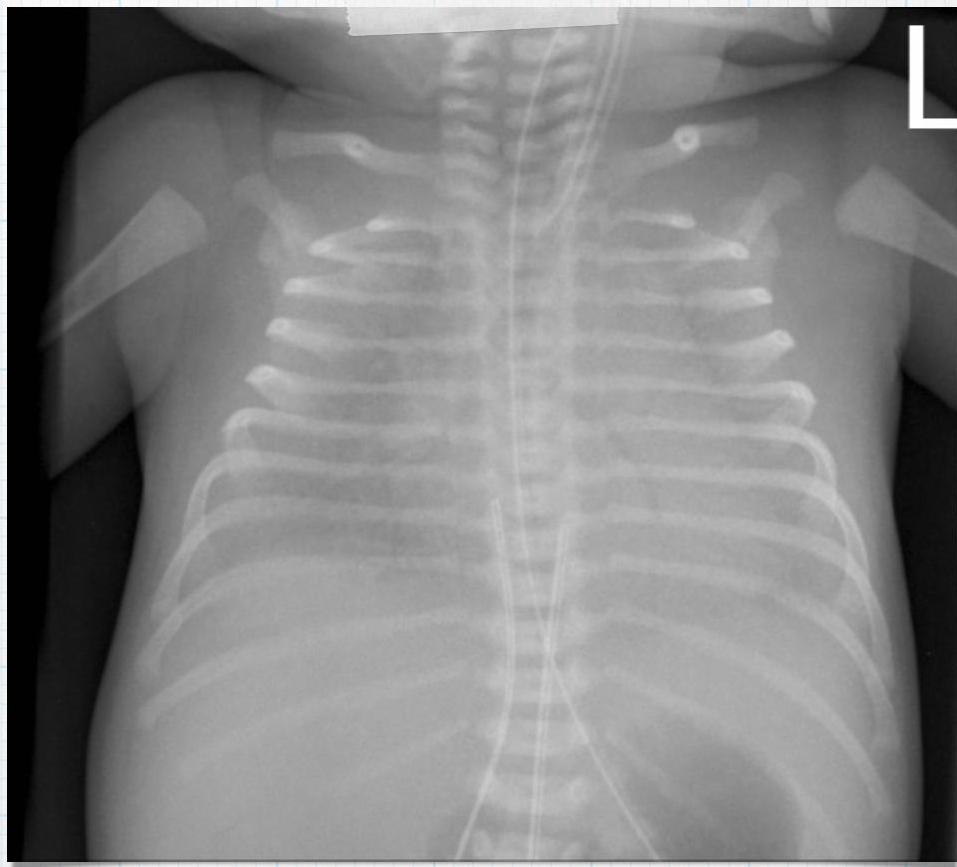

Preterm Infant with Respiratory Distress

- Preterm 29 weeks gestation C/S delivery showed severe respiratory distress soon after birth - RDS

- Air bronchograms

-

There is a homogeneous opacification of both lungs with white-out lungs - (1 .field (grounds glass appearance) and air bronchogram bilaterally

.The diagnosis is Acute Respiratory Distress Syndrome (ARDS) - (2

- .I- Massive blood transfusions Preterm 29-weeks gestation C/S delivery showed severe respiratory distress soon after birth. This chest x-ray was taken at the age of 6 hours.

- Q1: Write 2 abnormalities in the X-Ray?

- Q2: What is the likely diagnosis?

- Q3: Write 2 management steps.

Answers:

- Q1: Ground glass appearance, wide intercostal space.

- Q3: Mechanical ventilation, give Surfactant for lungs maturation.

Respiratory Distress Syndrome (Premature Neonate)

X-ray? Ground glass appearance of the lungs with air bronchogram.

Diagnosis? Respiratory Distress Syndrome.